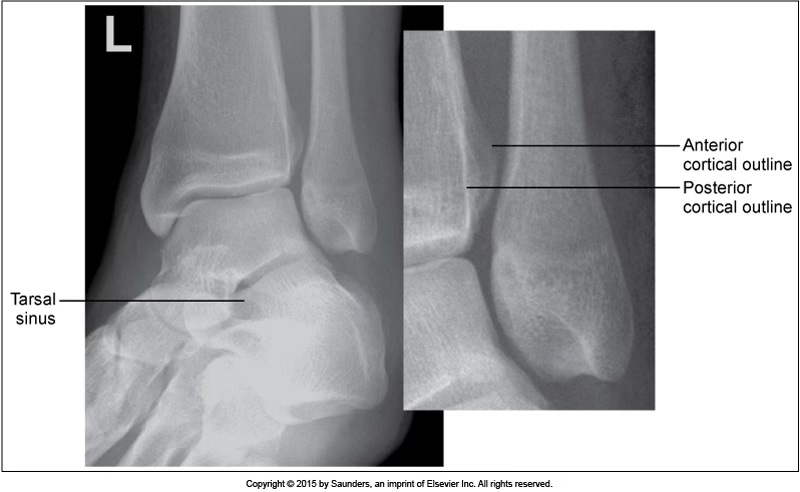

lateral ankle

accurate positioning

foot not dorsiflexed

leg externally rotated

sinus tarsi more open

fibula at the back of tibia

leg internally rotated

sinus tarsi closed

fibula not in center